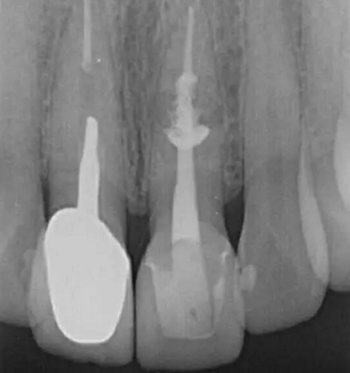

診斷:左上中切牙牙根內(nèi)吸收。治療計(jì)劃:左上中切牙根管治療,全冠修復(fù)。 治療過程:患者知情同意。使用含1/100,000腎上腺素的4%鹽酸阿替卡因(碧蘭麻,艾龍)局部浸潤(rùn)麻醉,橡皮障隔濕。去腐未盡露髓,露髓孔出血多。開髓,使用10#不銹鋼K銼(MANI,日本)探查根管,根管中段有鈣化物阻擋,不能達(dá)到牙根全長(zhǎng)(圖3A)。在顯微鏡下(Leica M400E,萊卡, 德國(guó)) 使用超聲尖(E1根管治療超聲尖,啄木鳥公司,中國(guó))通開,采用根管長(zhǎng)度測(cè)量?jī)x(Root ZX, Morita公司,日本)加診斷絲片法(圖1B)測(cè)量根管長(zhǎng)22 mm。使用控制扭矩馬達(dá)(X-smart,登士柏)和鎳鈦旋轉(zhuǎn)器械(Hero 642, Micromega)根管預(yù)備,根管預(yù)備過程中使用5.25%次氯酸鈉溶液沖洗。 根備完成后使用超聲蕩洗根管,5.25%次氯酸鈉溶液3 分鐘, 17% EDTA溶液1分鐘。干燥根管,使用螺旋充填器根管內(nèi)封氫氧化鈣糊,氧化鋅丁香油水門汀暫封。1周后患者復(fù)診,患者述無術(shù)后不適,檢查暫封完好,無叩痛,不松,牙齦無紅腫瘺管。使用橡皮障隔濕,去除暫封物,超聲蕩洗根管,5.25%次氯酸鈉溶液3 分鐘, 17% EDTA溶液1分鐘。干燥根管,牙膠尖(達(dá)雅鼎,中國(guó))和必蘭根充糊劑(Cortisomol, 艾龍公司,法國(guó))熱垂直加壓法根管充填。術(shù)后片顯示根充恰填,可見牙膠/糊劑被壓入鈣化物周圍和內(nèi)部縫隙內(nèi)

1月后復(fù)查無不適,行全瓷冠修復(fù)。8月2周后復(fù)查,患者無不適主訴,牙冠美觀,邊緣完好,患牙無叩痛,不松動(dòng),牙齦無紅腫瘺管, X線片示根周膜連續(xù),根尖周未見異常。建議患者避免用前牙撕咬食物,定期復(fù)查。 討論: 臨床上,由于牙根內(nèi)吸收和牙根外吸收的治療方法和預(yù)后不同,常需要對(duì)兩者進(jìn)行鑒別診斷。過去通常采用偏移投照的方法鑒別兩者。在偏移投照片上,外吸收病損和根管輪廓相對(duì)位置較正位片會(huì)發(fā)生變化,而內(nèi)吸收病損則不會(huì)[12]。